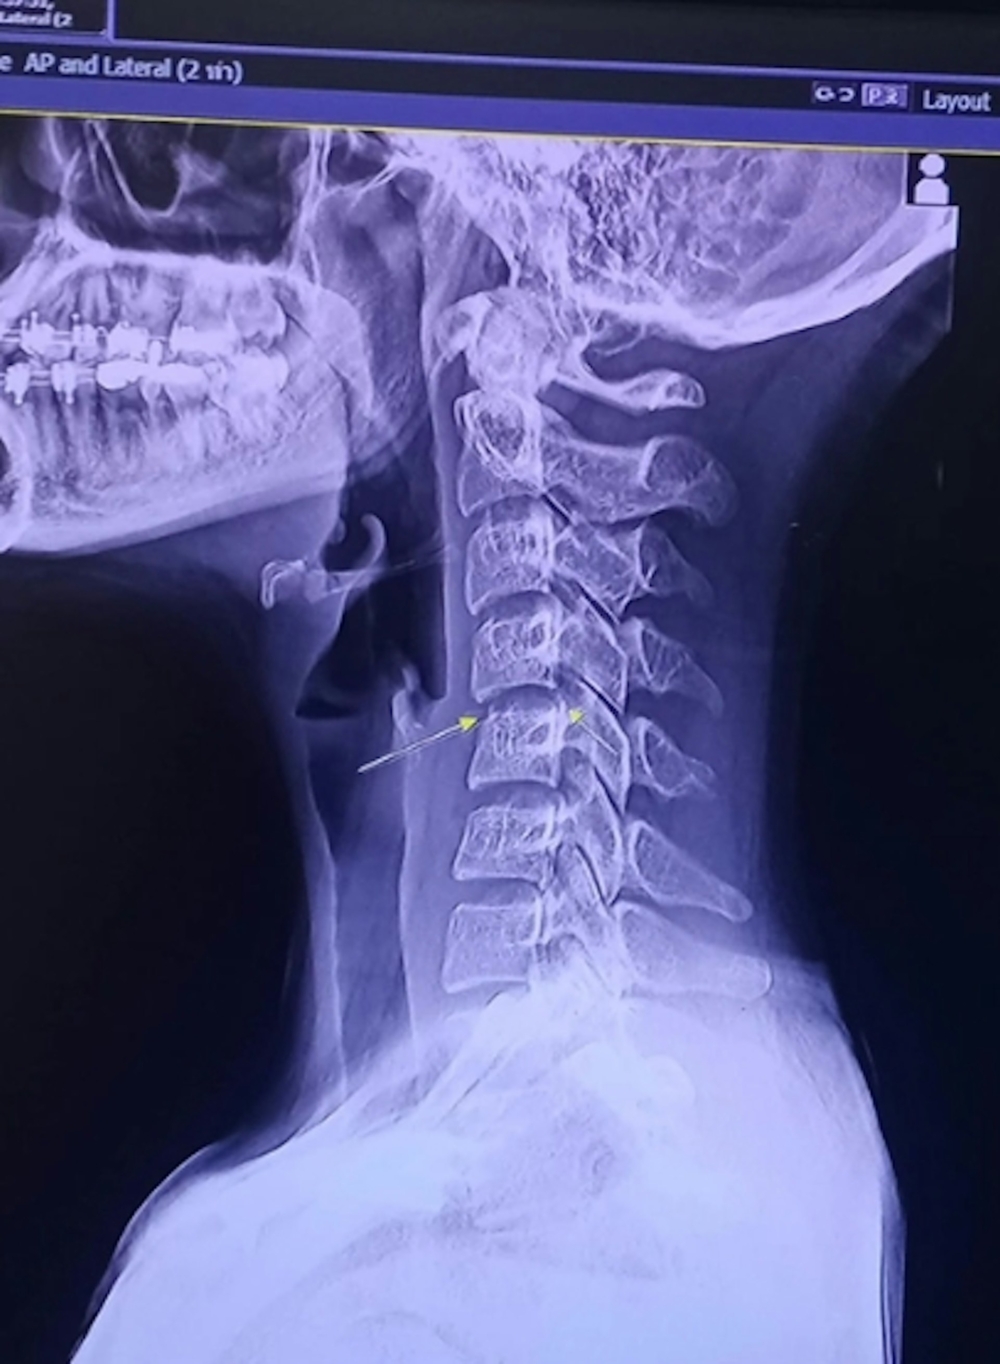

據指Chayada因媽媽也是按摩師,故她從小就很喜歡按摩,不曾懷疑過按摩的效果,因此又去了第三次按摩。然而直至情況惡化,她就醫時才發現原來頸椎早已受傷,在接受按摩後更導致神經受損,變成半身癱瘓,最後在臥床1個月後近日宣布離世。而泰國傳媒就稱,Chayada最後死於與血管感染和腦部腫脹有關的併發症,當地醫生亦促請按摩師不要為客人做「lock頸」,避免他們受傷。